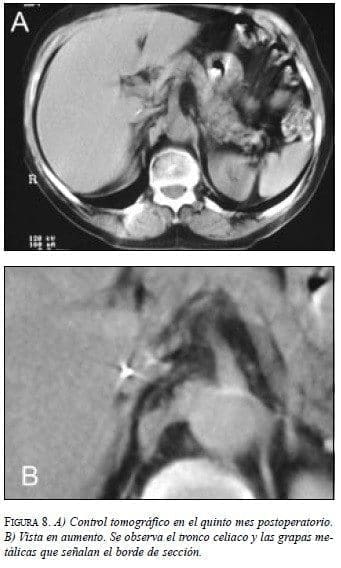

Los controles postquirúrgicos no han revelado recaída o progresión de la enfermedad, como lo muestra el TAC de control (figura 8). La paciente se encuentra asintomática y en buenas condiciones generales, sin síntomas asociados con síndrome carcinoide.